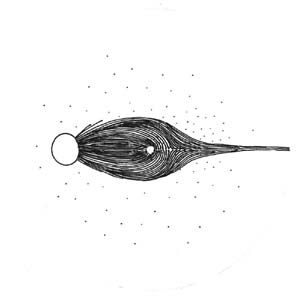

Výpadky nervových vláken na sítnici a graficky na perimetru podle Minclera

Lokalizovaný výpadek nervových vláken byl popsán poprvé teprve roku 1973 Hoytem. Je vějířovitého tvaru, připomínající ocas komety. Vyskytuje se u 20% glaukomů, není však pro glaukom specifický (drůzy, chorioretinální jizvy, dlouho trvající edém disku, pozánětlivá atrofie). Není u zdravých očí.

Korelace lokálního výpadku nervových vláken se změnami zorného pole dle Minclera

Když exkavace zasahuje až okraji terče dochází k poškození vláken, která vedou až do temporální části sítnice k tělům gangliových buněk, uloženým v sousedství horizontálního švu. Poškození těchto buněk a jejich axonů se projeví nasálním skokem s arkuátním Bjerumovým skotomem.

Pokud exkavace nedosahuje k samému okraji terče (miskovité exkavace), svědčí to pro poškození vláken z povrchnější vrstvy, které směřují k gangliovým buňkám uloženým paracentrálně – periferně od makulopapilárního svazečku. Poškození těchto buněk a jejich axonů se projeví paracentrálními skotomy.